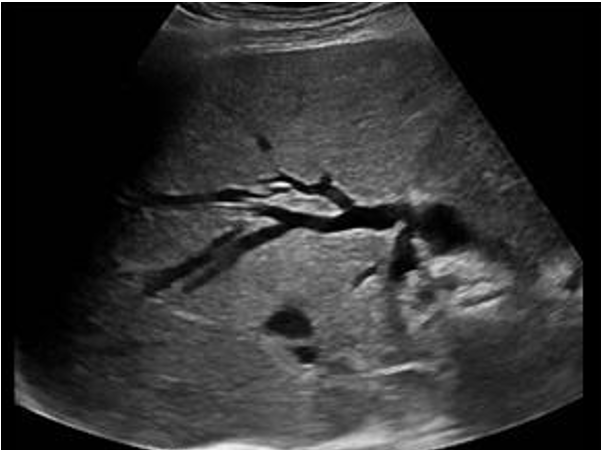

3) 복부 US: 간내담도 확장 확인 가능 (종양 자체를 찾기는 어려운 경우가 많음)